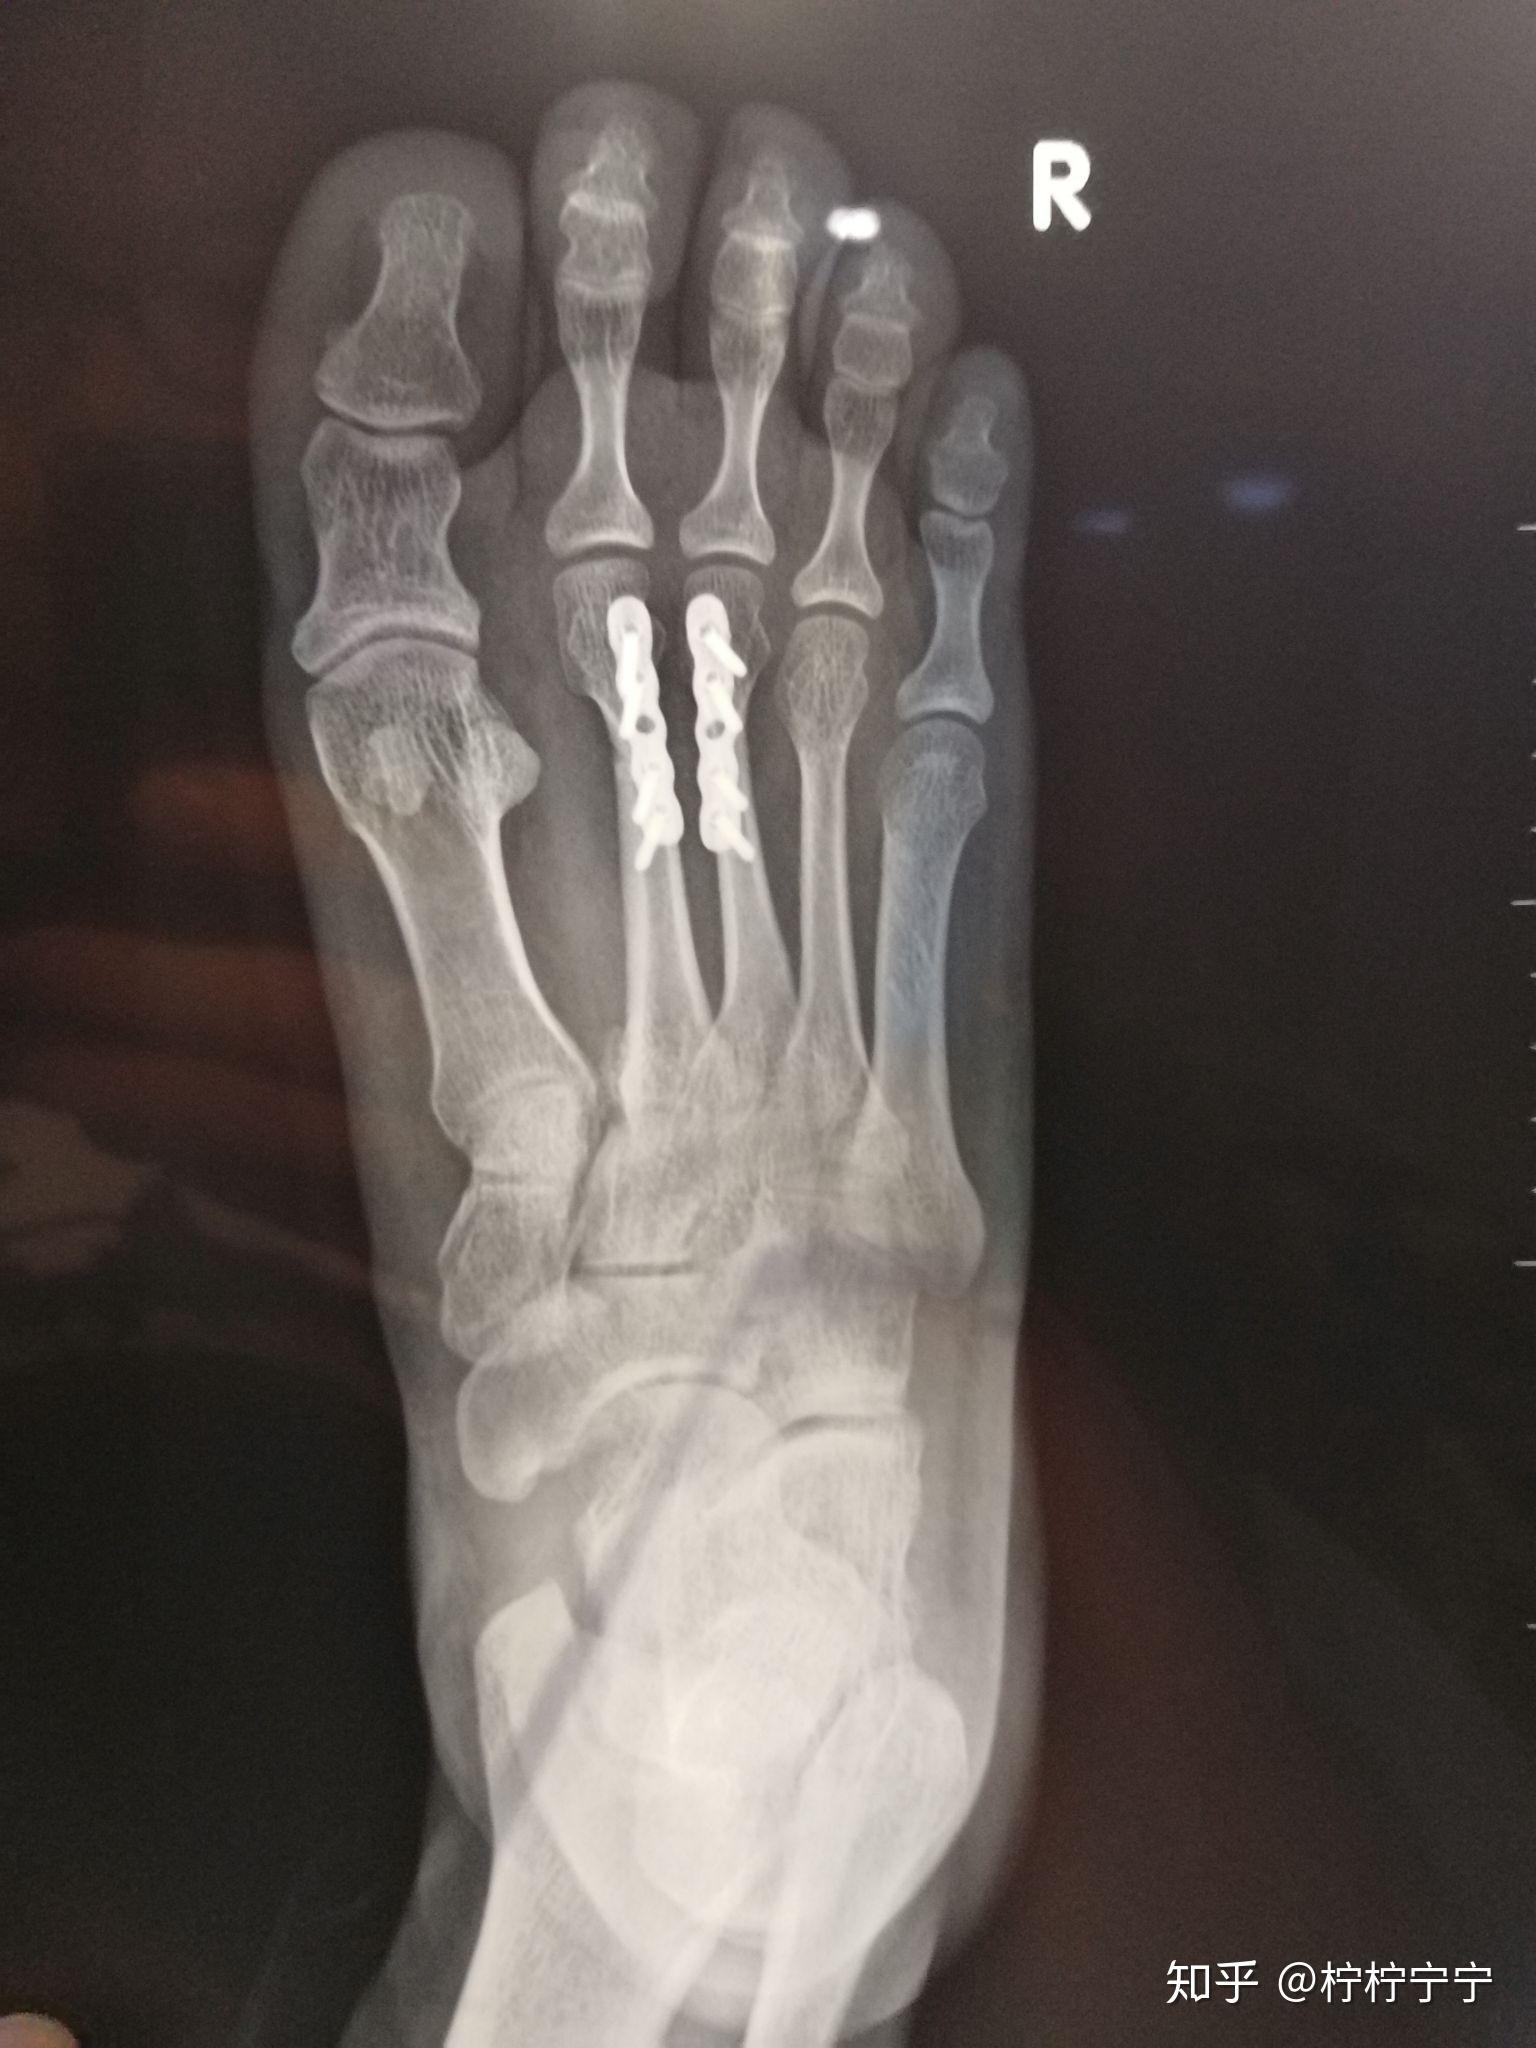

右足多发性跖骨骨折伴跗跖关节脱位以及骨筋膜室综合征的治疗 - 病例

右脚第一跖骨基底部骨折日志(右脚lisfranc损伤) - 知乎